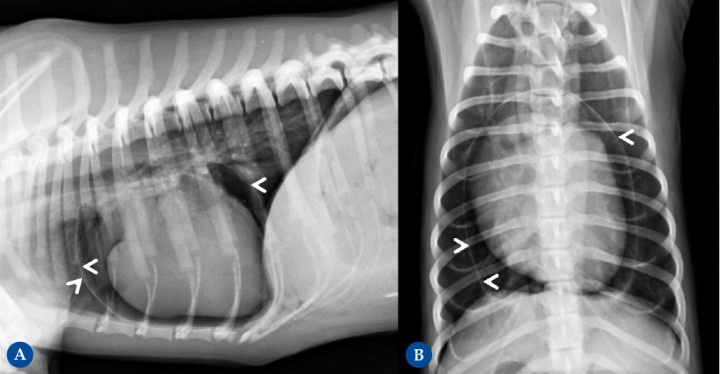

Figura 11

(A) Proyección lateral izquierda. (B) Proyección lateral derecha. Cruce de Labrador, hembra castrada, 9 años. Hernia peritoneo-pericárdico diafragmática conteniendo parte del hígado, vesícula biliar y grasa falciforme. Hallazgo incidental sin sintomatología asociada, se detecta como parte de protocolo diagnóstico neurológico por posibles convulsiones. Aspecto globoso de la silueta cardíaca que presenta un aumento moderado del tamaño, unos márgenes redondeados en las diferentes proyecciones ortogonales y un desplazamiento dorsal de la tráquea. Se observa signo de silueta entre el margen caudoventral de la silueta cardíaca y el diafragma (flecha negra). La silueta cardíaca presenta una opacidad mixta tejido blando y grasa, con la presencia de una área aproximadamente nodular de opacidad tejido en el margen caudal, ventral a la vena cava caudal en las proyecciones laterales (6ª espacio intercostal) (flechas negras punteadas). Además, se detecta presencia de contenido de opacidad grasa (círculo punteado). En el abdomen craneal incluido, se detecta una disminución evidente del tamaño de la silueta hepática (signo del abdomen vacío) [círculo blanco], sin visualizarse el aspecto ventral de los lóbulos hepáticos y con un desplazamiento craneodorsal marcado del eje gástrico (región pilórica) (la línea blanca representa el eje gástrico desplazado; debería ser paralelo a las costillas, perpendicular a la columna vertebral).